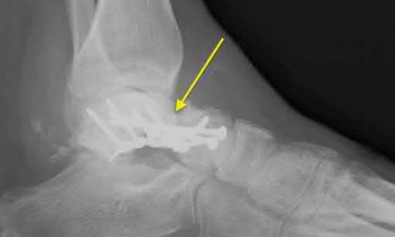

A 25-year-old male sustains an ankle fracture dislocation and undergoes open reduction and internal fixation. He returns to clinic five months following surgery complaining of continued ankle pain and instability with weight bearing. His immediate post-operative AP radiograph is seen in Figure A. Which of the following could have prevented this patient from developing persistent pain?

The patient presents with continued ankle pain and instability following open reduction and internal fixation. The radiograph in figure A demonstrates inadequate restoration of fibular length, likely leading to continued tibiotalar instability.

Illustration A demonstrates fibular malreduction with dislocation of the fibula anterior to the tibial incisura. Illustration B shows a comminuted fibula fracture along with a measurement of length from an intact fibula. The arc from the lateral process of the talus to the peroneal groove of the distal fibula is known as the "dime" sign and should remain unbroken if fibular length has been restored. Illustration C demonstrates the use of a push-pull screw and lamina spreader to regain length intraoperatively for a comminuted fibula fracture.